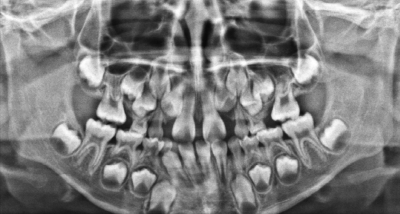

7歳の男児。抜歯の経験はないが、最近4本の乳歯が自然脱落したという。オーバージェットは +2mm、オーバーバイトは +1mm である。初診時のエックス線画像を別に示す。

永久歯の萌出に異常がみられる部位はどれか。2つ選べ。

a. 上顎前歯部

b. 下顎右側臼歯部

c. 下顎左側臼歯部

d. 上顎右側臼歯部

e. 上顎左側臼歯部